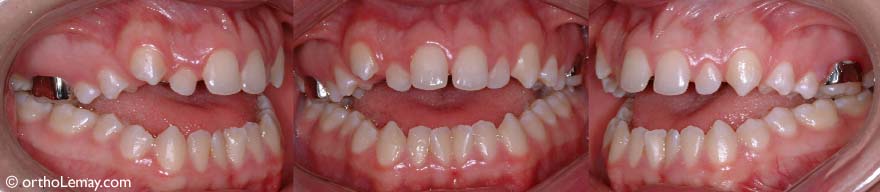

Sévère béance antérieure nécessitant de l’orthodontie et une chirurgie pour corriger la mauvaise relation entre les mâchoires d’un garçon de 17 ans.

Fermeture de la béance antérieure à la suite de l’orthodontie et d’une chirurgie aux mâchoires. Il en résulte une meilleure fonction (mastication et phonétique).